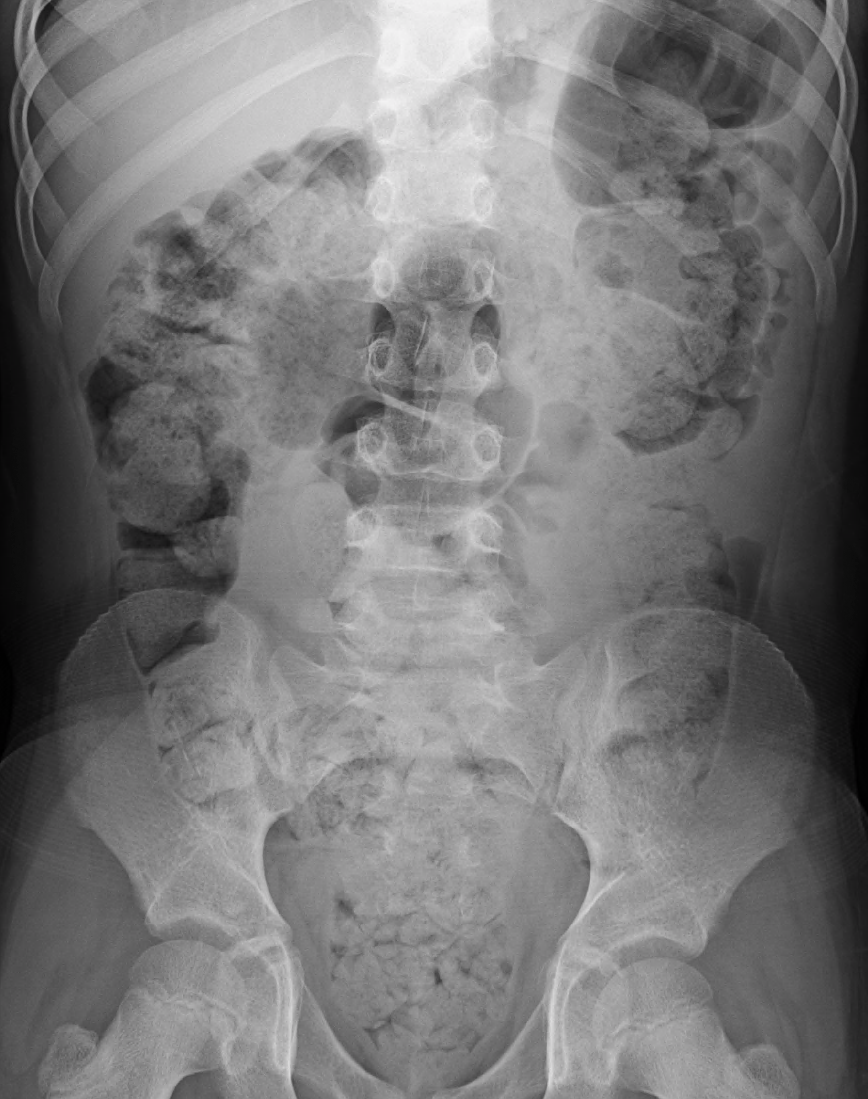

복부 X선 촬영은 일반적으로 장폐색이 의심되는 경우에만 시행되며, 대장 내 광범위한 딱딱하게 굳은 변을 보여줄 수 있으며, 유사한 증상의 다른 원인을 확인하거나 배제할 수 있다.[24][16] 종양과 같은 대장 이상이 의심되는 경우 대장내시경 검사가 시행될 수 있다.[14] 드물게 시행되는 다른 검사에는 항문직장 압력 측정술, 항문 괄약근 근전도 검사 및 배변 조영술이 포함된다.[16]

문진과 신체 검사를 통해 소화관 자체의 병변이 원인인 기질성 변비와 증상성 변비를 감별한다. 복부 X선 촬영은 대장 상태를 신속하고 객관적으로 확인할 수 있으며, 침습이 적은 검사이므로 우선적으로 선택된다. 특히 “최근 상황”, “대장암 가족력”, “체중의 급격한 변화”, “직장 출혈”, “50세 이상” 중 하나에 해당하고 기질성 변비가 의심되는 경우 대장내시경 검사가 선택된다.